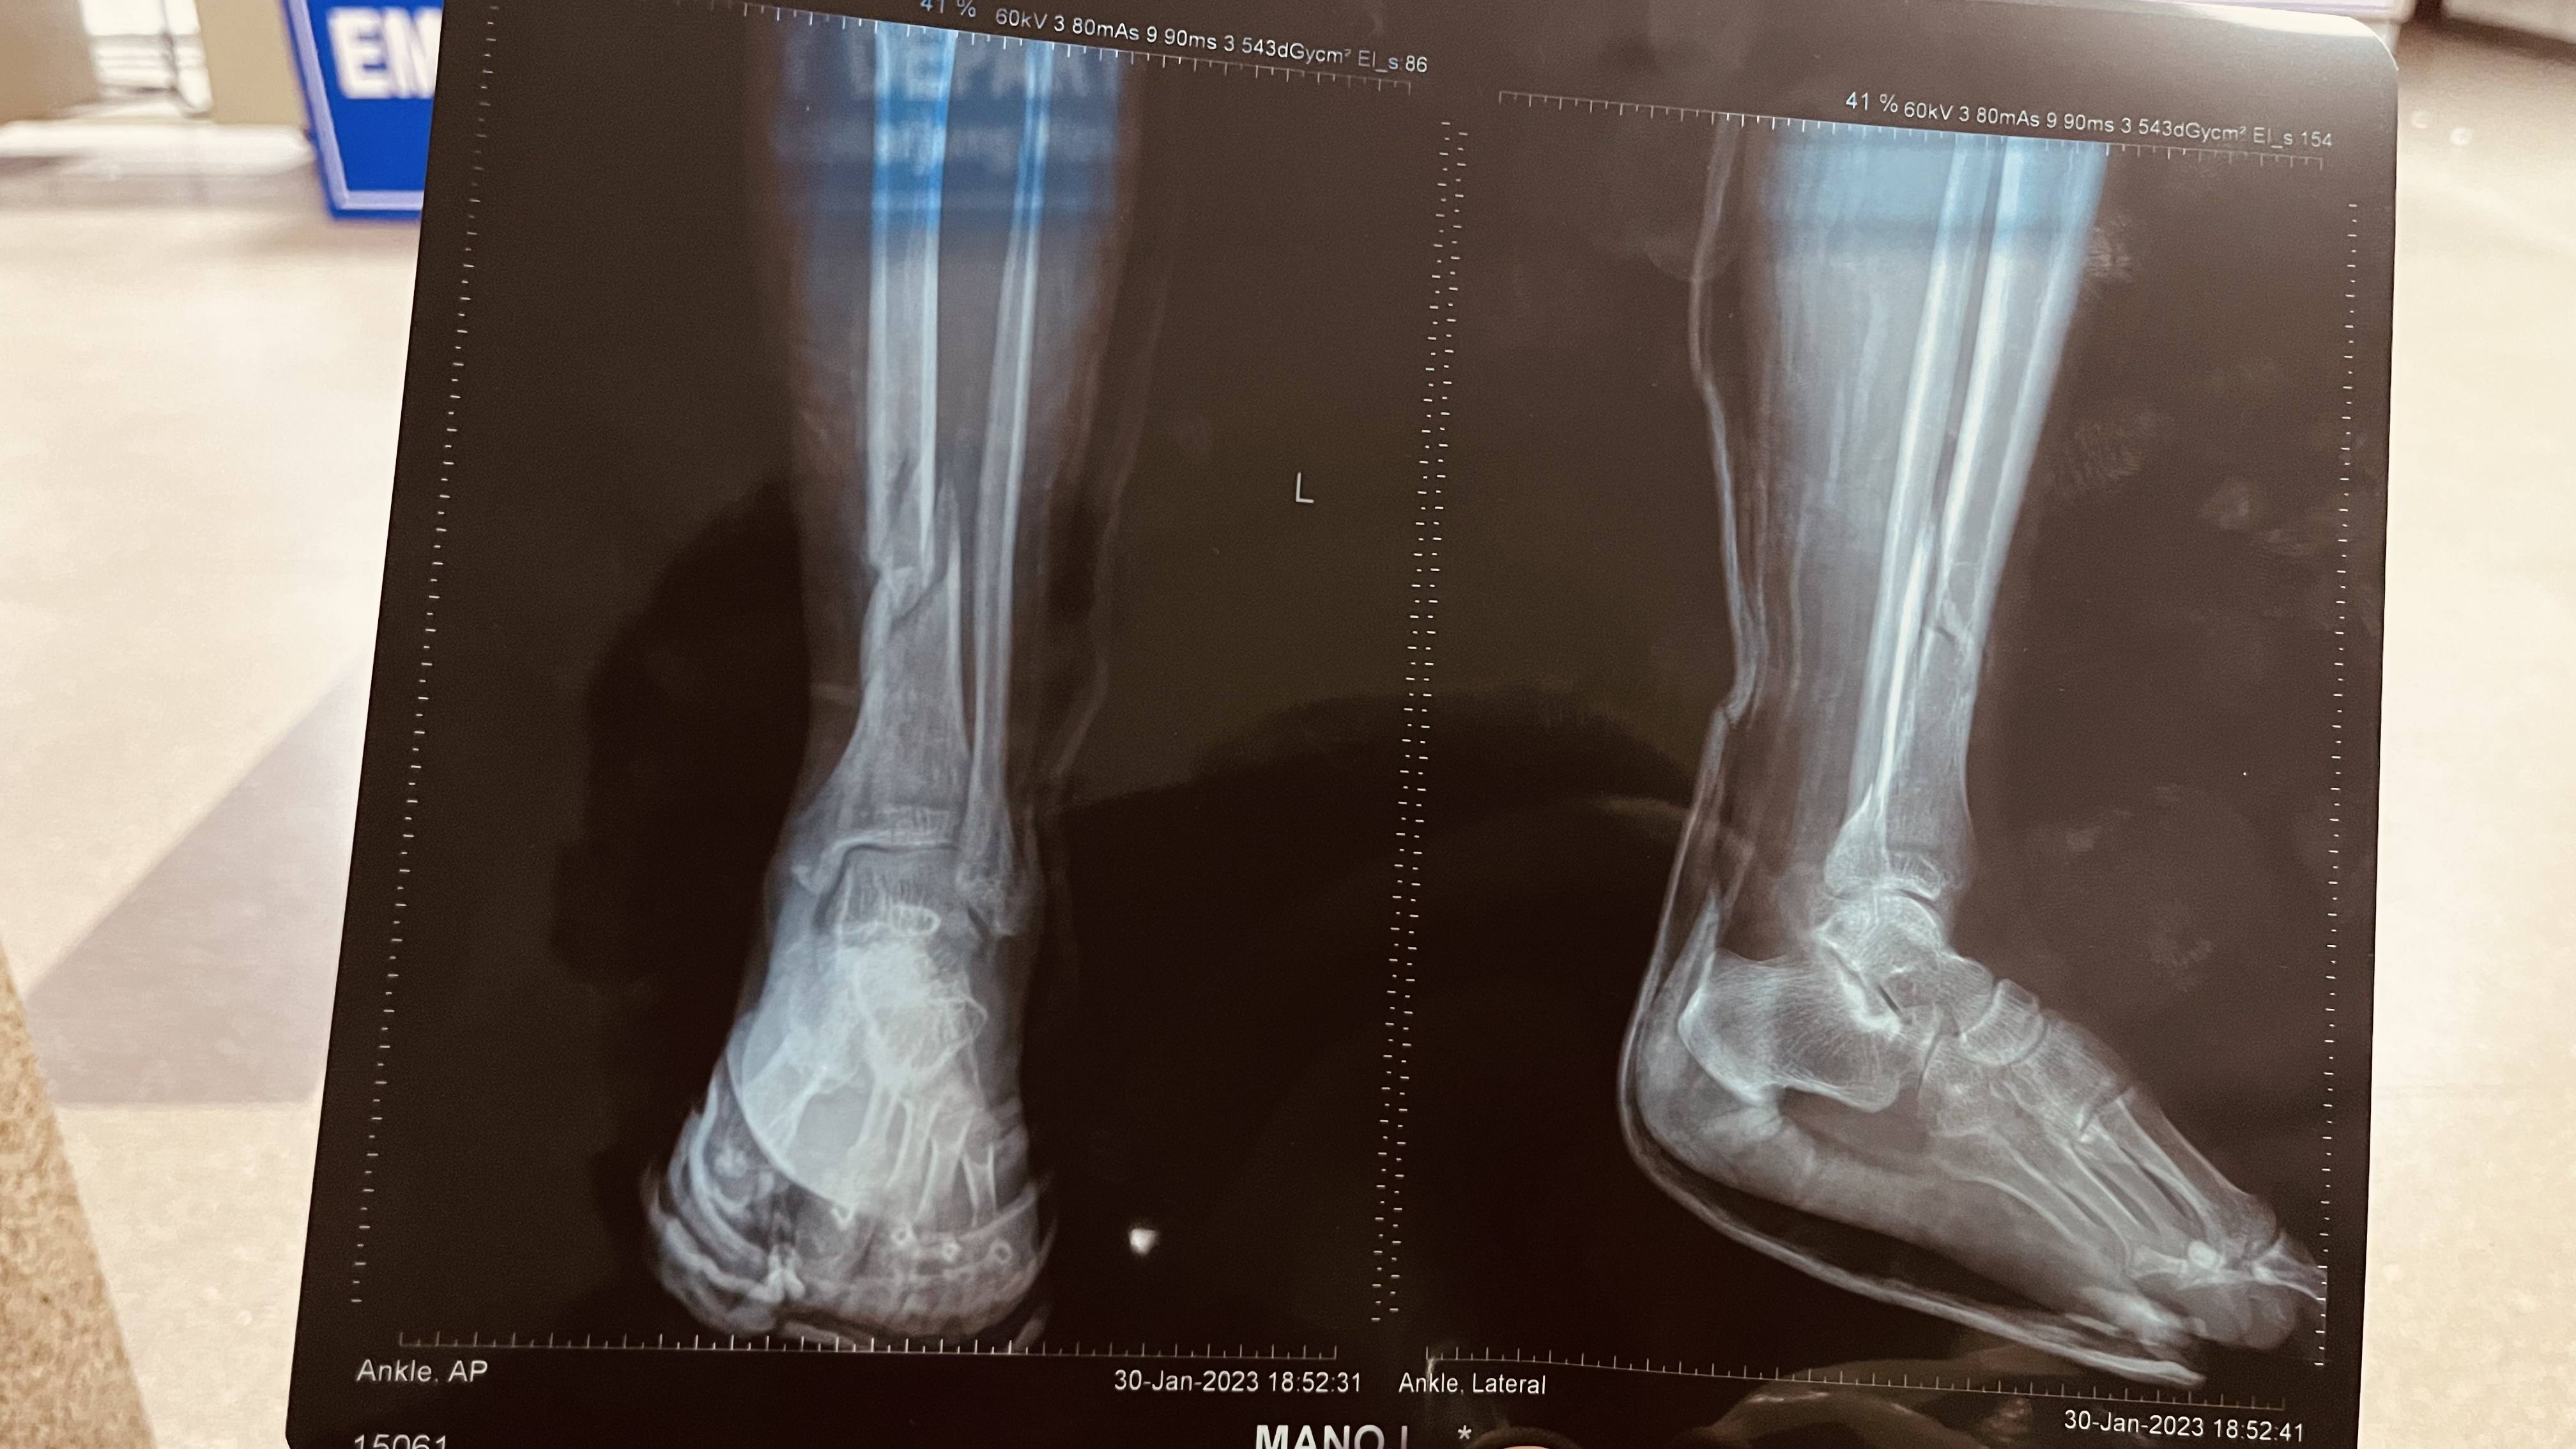

leg fracture-tibia and fibula

mere fibula and tibia me fracture h,fibula teak ho gya h but tibia me abhi recover nhi hua h.

x ray me dekh raha hu gap jyada h lekin jab side view dekh rha hu to bilkul bhi nhi h mujhe bataye.

tibia me lower side me h yeh fracture

doctor bta rha h sgar jldi teak hona h to surger else automatic recover ho rha h

please ek baar x ray dekh kar bataye